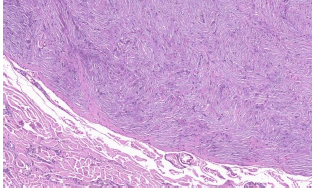

O Tumor muscular liso de potencial maligno incerto do corpo uterino é uma categoria heterogênea. Em relação a esta entidade patológica, assinale a alternativa correta.

À microscopia, neoplasia mesenquimal benigna trifásica, constituída por células fusiformes musculares brandas, vasos hialinizados de paredes espessadas e tecido adiposo maduro. Este tumor pode ocorrer em diversas localizações. Assinale a alternativa que apresenta qual a localização mais frequente deste tumor.